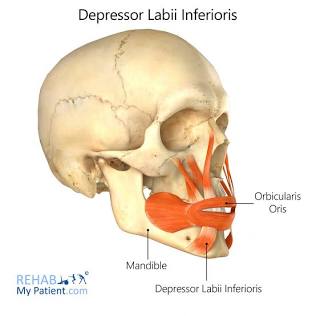

Depressor

Produces inferior movement.